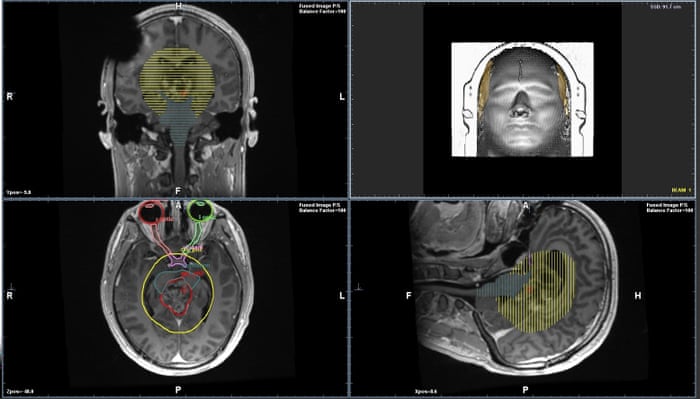

Scans For Diagnosis The Brain Tumour Charity